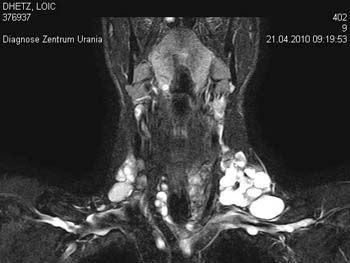

Bei besonders grossen Strumen, vor allem bei Ausbreitung in den Brustkorb, hinter die Luftröhre oder die Speiseröhre ist für die Operationsplanung des Chirurgen eine sogenannte Schnittbilduntersuchung wichtig. Computertomographie (ohne Kontrastmittel !!) können wichtige Zusatzuntersuchungen vor einer Operation sein.

|

Magnetresonanztomographie |

ein SPECT-CT |